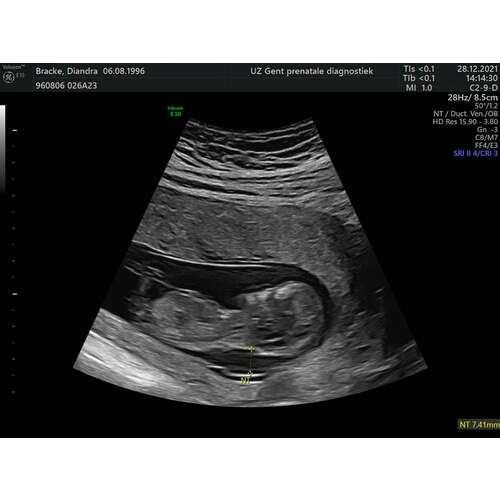

Wij hadden met bijna 12 weken een nekplooi van 5.5mm. Dit was helaas geen goed nieuws, wij hebben met 15+3 een vruchtwaterpunctie laten doen en daar kom onherroepelijk uit dat ons zoontje trisomie 21 had. Wij hebben toen de hartverscheurende beslissing gemaakt om de zwangerschap af te breken omdat

op voorhand niet duidelijk kan worden hoe erg hij eraan toe is en wij dit niet voor ons kindje wilden.

Nekplooi zat ondertussen op goede 7mm, specialisten niet zo positief..

Op basis van de echo foto zou ik er vanuit gaan dat het om het Down Syndroom gaat. De nekplooi is wel echt behoorlijk, daarnaast lijkt het gezichtje van jullie kleintje ook afgeplat en is er mijn inziens geen overduidelijk neusbotje zichtbaar.

Precues zoals het bij ons zoontje ook was, al had ons zoontje het zelfs nog iets minder opvallend naar mijn idee.. en dit bleek inderdaad om het Down Syndroom te gaan.